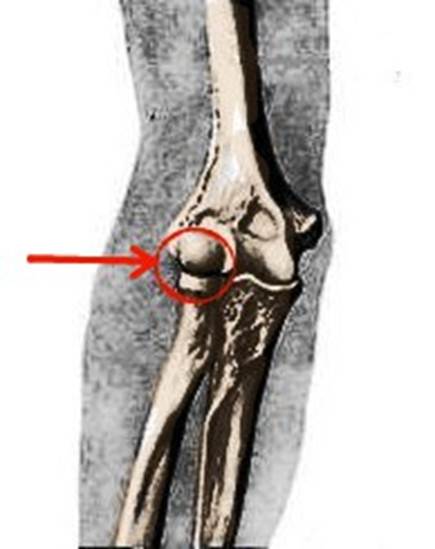

S: На рентгеновском снимке изображен articulatio cubiti (латинский язык).